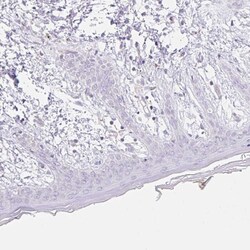

- Immunohistochemical analysis of CLEC3A in human skin using CLEC3A Polyclonal Antibody (Product # PA5-62424) shows negative cytoplasmic positivity in fibroblasts as expected.